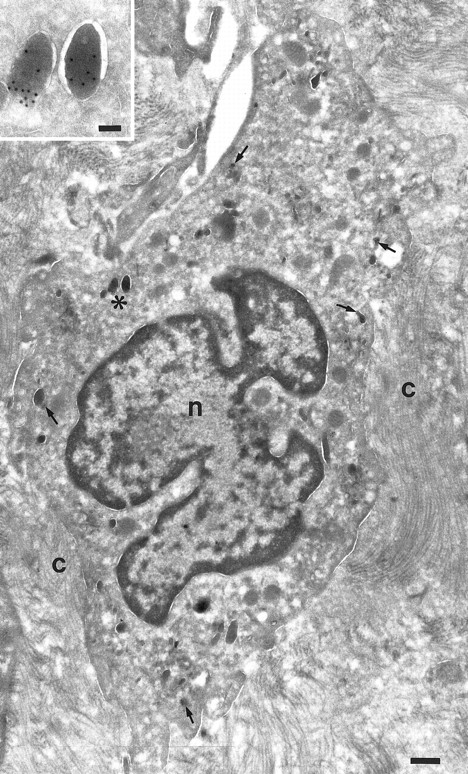

Localization of TGF-α in macrophages. Cryosection of a macrophage from a nasal polyp labeled for TGF-α. A few granules are labeled for TGF-α (arrows). Nucleus, (n); bundles of collagen (C). Inset is a higher magnification of the marked granules (asterisk) to show the gold labeling. Bars = 500 nm, inset = 100 nm.

In promonocytes from the bone marrow, as well as monocytes from bone marrow and peripheral blood, TGF-α was localized in abundant electron-dense granules (Figs 1 and 2). The pattern of granules was similar in bone marrow promonocytes (Fig 1) and mature monocytes (Fig 2). These cells can be distinguished by the presence of bundles of filaments in the cytoplasm and a rounded or oval nucleus in promonocytes. Indications for the release of TGF-α–positive granules came from monocytes incubated for 24 hours with IL-10 and IFN-γ and thereafter labeled with anti–TGF-α. At the ultrastructural level, these monocytes have an activated appearance (Fig 3): ruffles on the cell membrane on one side, the nucleus localized at the opposite side and less TGF-α–positive granules than in untreated cells. Moreover, the remaining TGF-α containing granules are located underneath the cell membrane, mainly under the ruffles. Macrophages in nasal polyps (Fig 4) contained very few TGF-α–positive granules.